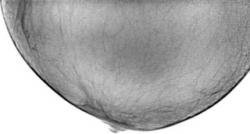

Иллюстрации 1, 2, 3 – варианты цифровой обработки изображения правой молочной железы.

Общая скиалогическая картина инволютивной железы. В параареолярной области, интимно примыкая к ареоле, определяется снижение прозрачности неправильной формы, довольно однородной структуры, с неровной, нечеткой границей с окружающей тканью. Контур кожи четко дифференцируется, он «интактен».

Иллюстрации 4, 5 – фрагменты с увеличением. Довольно четко дифференцируется «внутренний контур». От указанного участка четко визуализируются линейные структуры, направленные в сторону верхнего наружного квадранта.